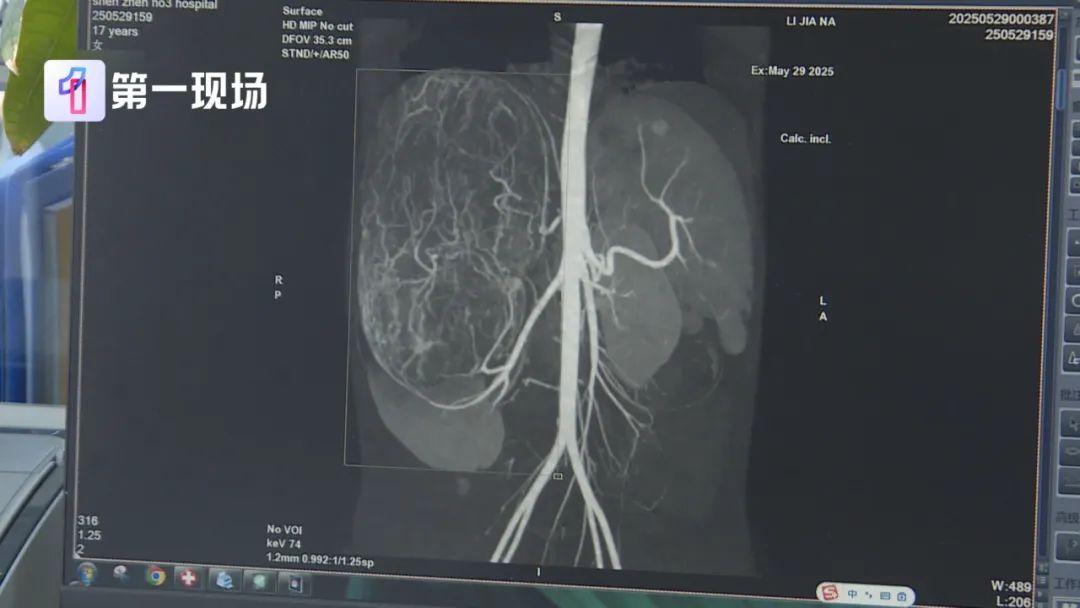

婷婷的肚子里

竟然长了一个巨大的肿瘤

直径长达27厘米

等到了当地医院一检查,CT结果显示,她的右肾有恶性肿瘤伴肝转移可能,家长就立即带着孩子来到深圳求医。

肿瘤已经到了肚脐的下缘,就是后腹直肌外侧,这种情况需安全地把肿瘤切除,不要把肿瘤搞破,是我们首先要考虑的问题。

肿瘤切出来后,我们测量了大小有27公分,重量有2.435公斤,非常非常的大。